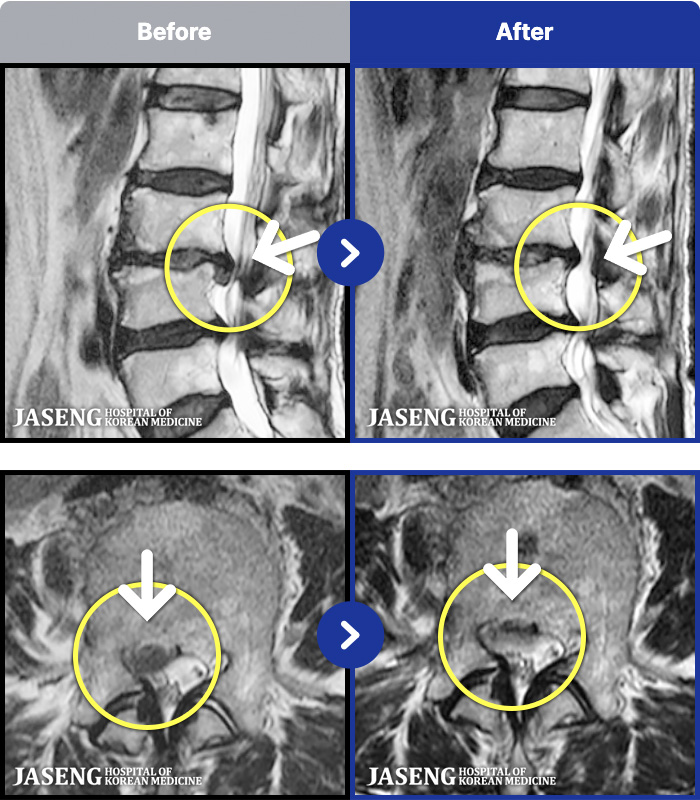

MRI ġ

MRI ũ ʸ Ȯϼ.